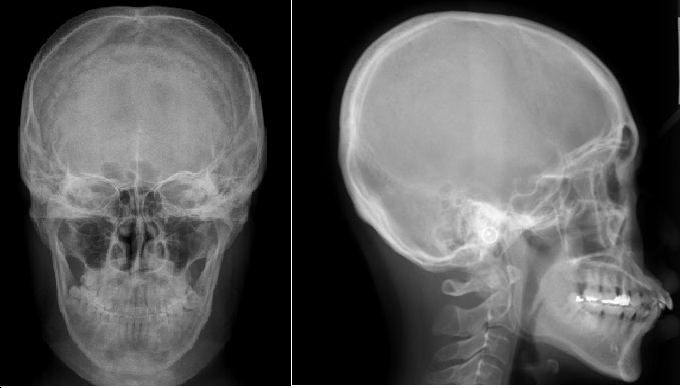

A telerradiografia lateral e frontal é um exame fundamental para a análise cefalométrica, permitindo a avaliação detalhada das bases ósseas, do crescimento facial e da relação maxilomandibular. Sua aplicação vai além da ortodontia, sendo essencial para planejamento de cirurgia ortognática, diagnóstico de assimetrias faciais e avaliação de distúrbios respiratórios.

Com imagens de alta definição e baixa distorção, a telerradiografia possibilita medições precisas e comparações evolutivas, auxiliando o dentista no planejamento e monitoramento de tratamentos de longo prazo.